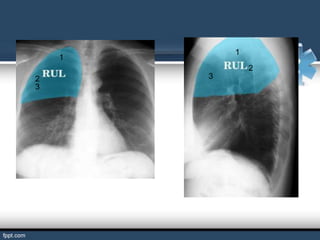

BRONQUIOS SEGMENTARIOS

Son ramificaciones de los bronquios lobulares.

El hombre tiene 18 bronquios segmentarios que estos se ramifican

en bronquiolos.

Si los bronquios segmentarios ya no se puede subdividir se le llama

bronquiolo terminal.